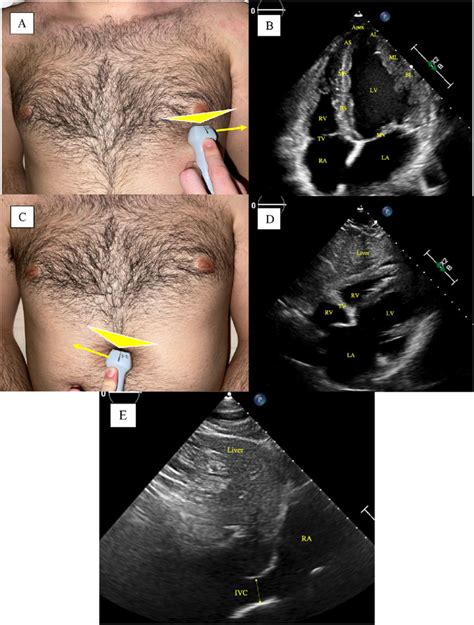

Finding the Sweet Spot: Optimal Probe Placement for the 5-Chamber View

Alright team, let’s get down to the nitty-gritty of probe placement for that awesome 5-chamber view . This is where the magic happens, guys! You’ll typically want to start at the apical window . Think of the apex of the heart – that’s your target zone. Position the transducer at the left lateral chest wall , usually between the fifth and sixth intercostal spaces . Sometimes, you might need to go a little higher or lower, or more medially or laterally, depending on your patient’s body habitus. The key here is to aim the transducer towards the patient’s right shoulder . This orientation is super important because it allows the ultrasound beam to pass through the heart without being significantly blocked by the lungs or ribs. Imagine you’re trying to get a direct line of sight to the heart’s core. Now, the initial placement might give you a 4-chamber view. That’s a great starting point! From there, you’ll need to make subtle adjustments. The goal is to rotate the transducer slightly counter-clockwise (think of the indicator dot on the probe pointing towards the patient’s left axilla) while maintaining that apical position. This subtle rotation is what brings the aortic valve into view, effectively transforming your 4-chamber view into the coveted 5-chamber view. You’re essentially peeking over the left atrium to get a glimpse of the aortic outflow tract. Remember, you’re looking for a clear image of the left ventricle, left atrium, mitral valve, and the aortic valve, all in the same plane. The interventricular septum should be on your left, and the left atrial wall on your right. The aortic valve will be seen superiorly and slightly to the left of the mitral valve. Fine-tuning is everything. Small tilts and shifts can make a huge difference in image quality. Don’t be afraid to gently fan the transducer or adjust the depth and gain controls to optimize what you’re seeing. The goal is a symmetrical-looking left ventricle, with well-defined walls and clear visualization of all four chambers and the aortic valve. Practice makes perfect, so keep trying different angles and positions until it feels intuitive. You’ll know you’ve got it when you can see the mitral valve leaflets opening and closing, and the aortic valve opening during systole. This view is crucial for assessing mitral regurgitation, aortic stenosis, and the overall function of the left side of the heart. It’s the integration of anatomical understanding with hands-on manipulation that truly elevates your echocardiography skills. Patient positioning can also play a role; a left lateral decubitus position often facilitates better apical access. However, always adapt to the patient’s ability to tolerate different positions. The depth setting on the ultrasound machine is critical; you want to ensure the entire heart is displayed without excessive surrounding tissue. Similarly, the gain settings need careful adjustment to differentiate between the endocardium, myocardium, and blood pool, avoiding both under-gaining (poor visualization) and over-gaining (flash artifacts or loss of detail). Patience and persistence are your best friends here. It might take a few tries, or even a few minutes, to achieve the optimal view, especially in patients with certain body types or lung disease that can impede ultrasound transmission.